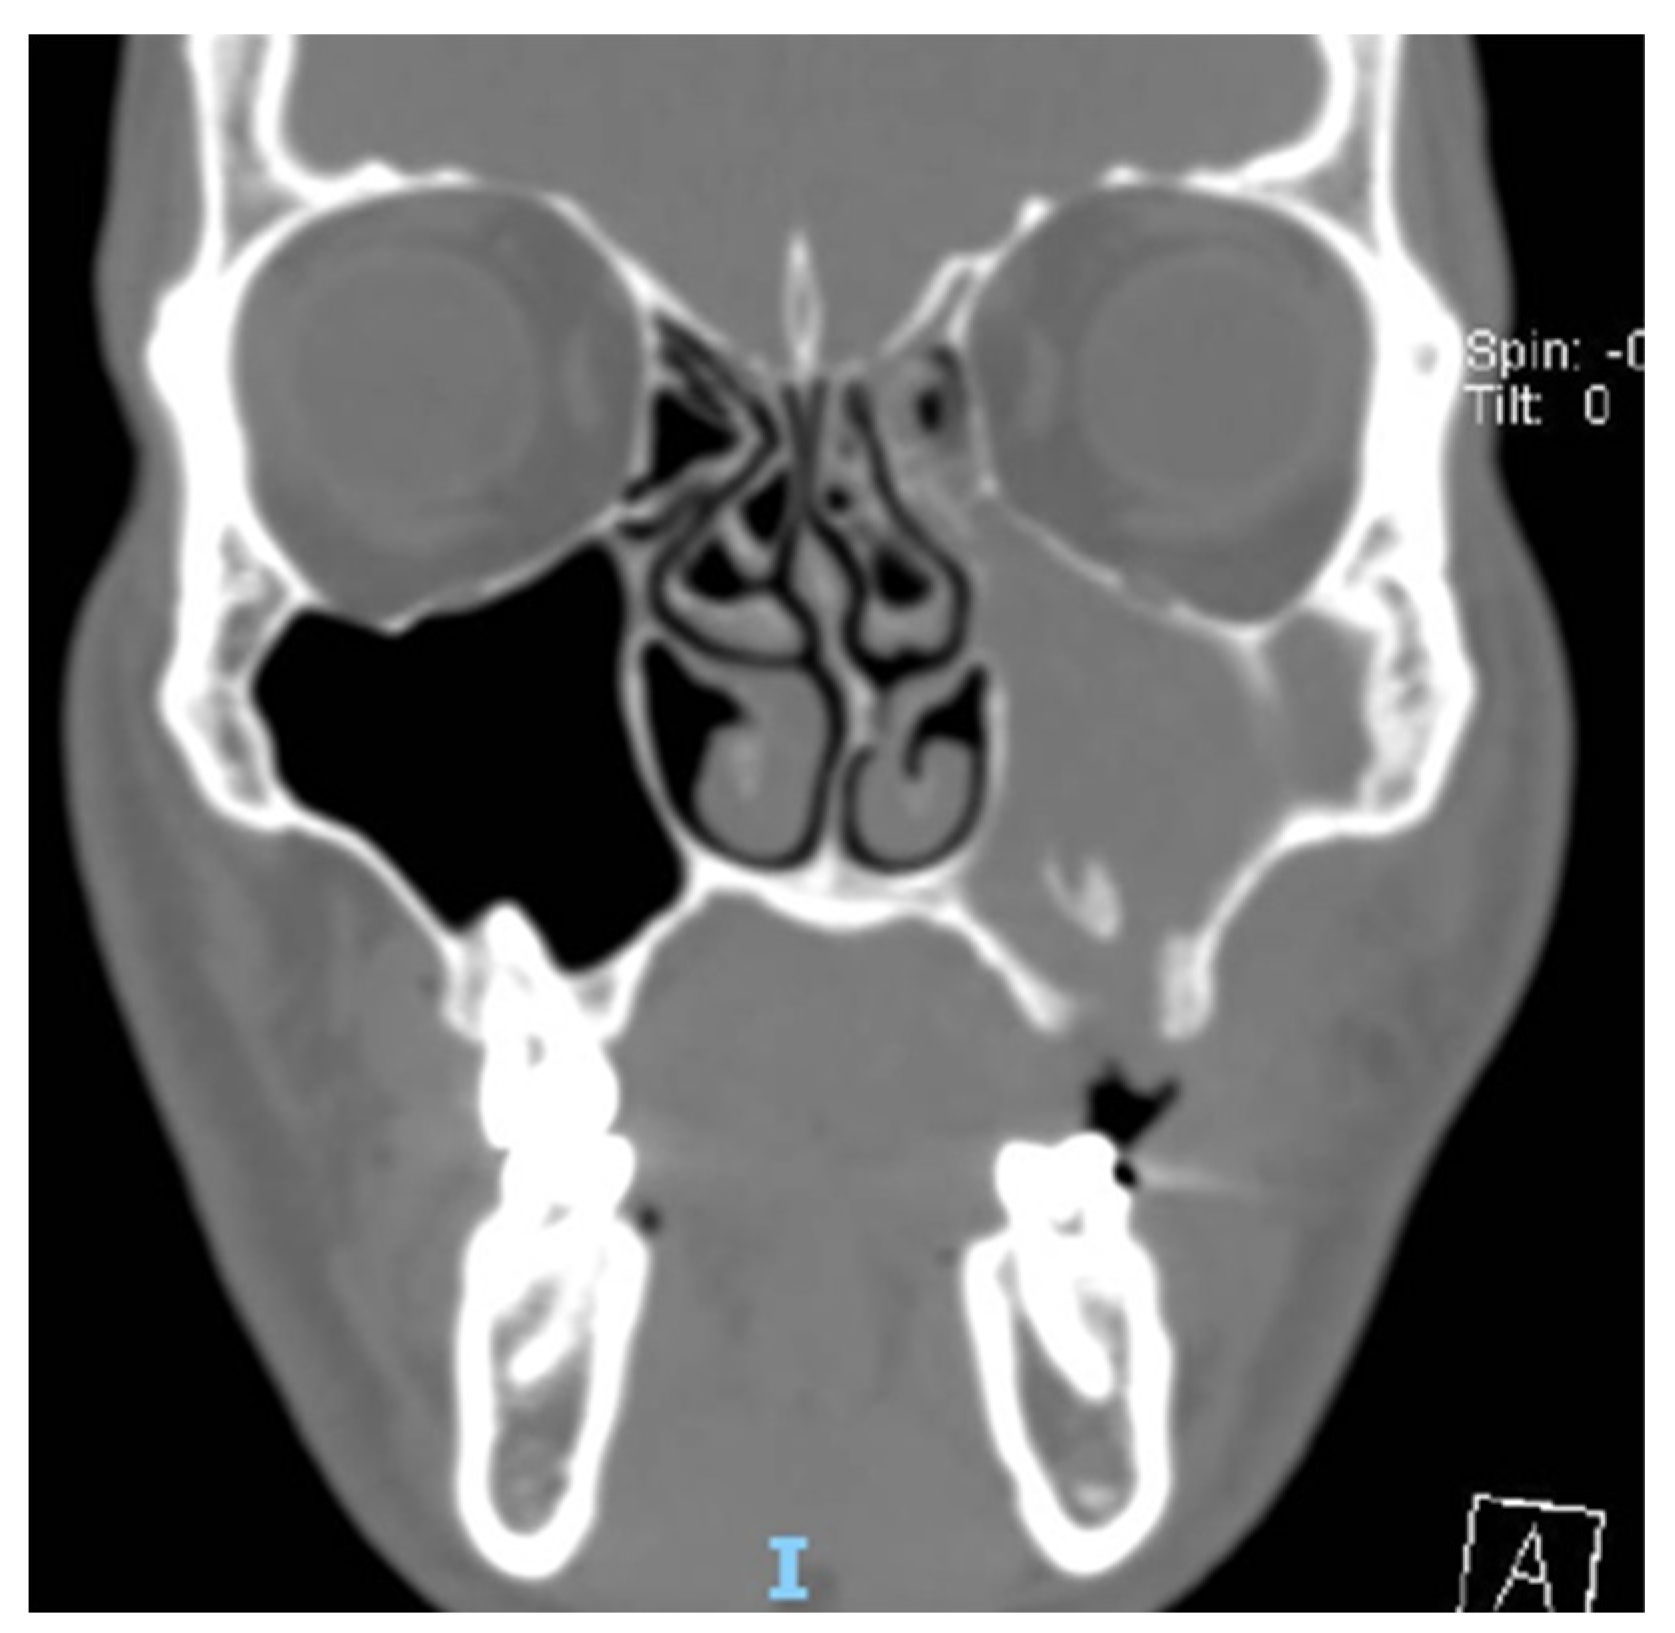

CT evaluation odontogenic origin causing obstructive maxillary Odontogenic Sinusitis Symptoms the present paper aims to present the etiopathogenesis, bacteriology, clinical manifestations, as well as treatment of. — the clinical presentation of odontogenic sinusitis varies, but most. sinusitis is a clinical diagnosis that relies on the presence of signs and symptoms such as facial pain/pressure/fullness, mucopurulent nasal. odontogenic sinusitis symptoms and care. Symptoms of ods include a. Odontogenic Sinusitis Symptoms.